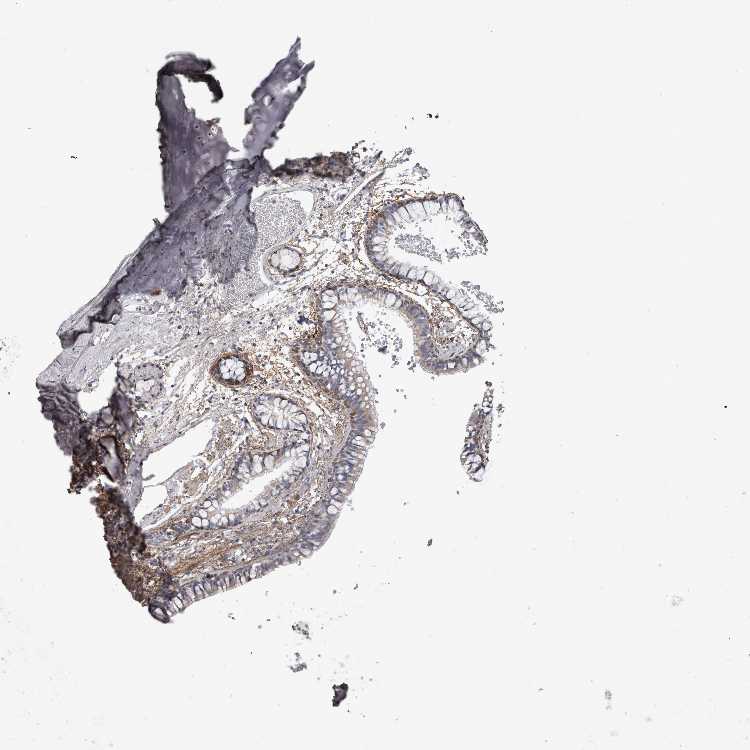

ADIPOSE TISSUE - Antibody stainingi

Antibody staining in the annotated cell types in the current human tissue is reported as not detected, low, medium, or high, based on conventional immunohistochemistry profiling in selected tissues. This score is based on the combination of the staining intensity and fraction of stained cells.

Each image is clickable and will lead to virtual microscopy that enables deeper exploration of all samples and also displays staining intensity scores, fraction scores and subcellular localization as well as patient and tissue information for each sample.

Antibody HPA023270

Adipocytes Low